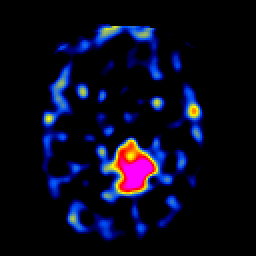

SPECT TL Study #5 -- Slice #32